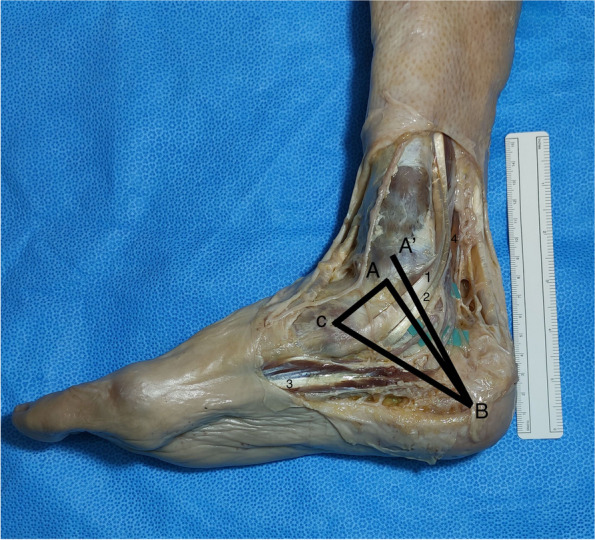

Methods: The distal part of the legs, ankles and feet of 12 Thiel embalmed cadavers were dissected. The pattern of the branches of the TN was registered and the measurements were performed according to the Dellon-McKinnon malleolar-calcaneal line (DML) and the Heimkes Triangle (HT).

Results: The TN divided proximal to DML in 87.5%, on top of the DML in 12,5% and distal in none of the feet. The Baxter's nerve (BN) originated proximally in 50%, on top of the DML in 12,5% and distally in 37.5% of the cases. There was a strong and significant correlation between the length of DML and the distance from the center of the medial malleolus (MM) to the lateral plantar nerve (LPN), medial plantar (MPN) nerve, BN and Medial Calcaneal Nerve (MCN) (ρ: 0.910, 0.866, 0.970 and 0.762 respectively, p <  0.001).